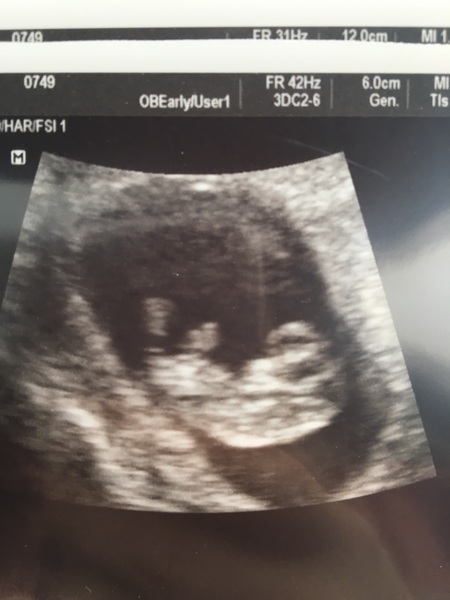

Hi all - happy bunny here, another early scan (my 3rd and last before the NHS one on the 16th).

Went great, heartbeat legs and arms all seen clearly, even forehead and nose.

Beautiful baby and he/she was even moving around a bit! Seems so real now we have even been and told some family this afternoon! Smile

10+5

Mrspage looking good there

What a lovely picture mrspage